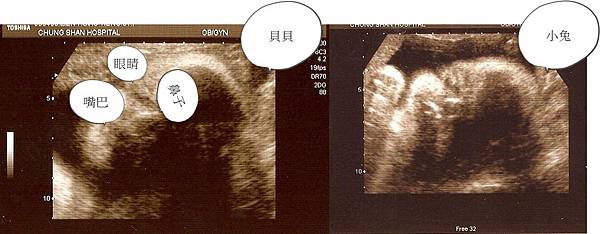

對啦 我都忘了發問 那個..... (真是拍謝) 正面的超音波到底要怎麼看阿 ? 為什麼阿姨我怎麼看都看不出來勒 還把我旁邊的那個半瓶水醫生拉來技術指導 可是 他說他也看不太出來 @@ 這樣一來真是只剩下1/3瓶水了我說 .... 是不是當了媽媽就自然會看了阿? 還是照的時後醫生會指導一下怎麼看阿? 阿姨我好好奇說~ :P

哈哈!我第一次也是媽咪教才看得出來阿!我把照片重新編輯一下,降你比較看得懂了嗎? (就是照片右邊是baby的額頭,左邊是嘴巴,右下方的陰影是baby的左半臉,所以只看得出右半臉...這需要一些想像力啦!妳跟Andy比賽一下誰比較厲害吧:p)